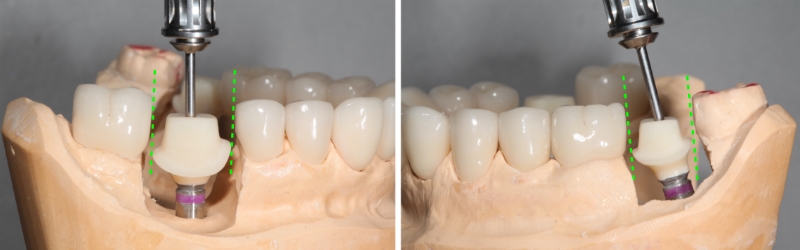

Additional challenges may be encountered when determining the best insertion path. Solutions can be reached through a possible change to the contour of:

- The adjacent interproximal surface

- The interproximal surface of the restoration.

The negative consequence of altering the implant restoration form interproximally to allow this surface to pass by the adjacent tooth is the opening of the interdental gingival embrasure, which may result in a lateral food impaction area.

If a restoration insertion path problem cannot be solved by altering an interproximal surface, a cemented restoration may be required. If a two-piece abutment and crown are fabricated, I want you to know that what goes into the implant dictates the insertion path in addition to the interproximal contacts of the adjacent teeth.

Suppose you fabricate a separate abutment and crown to cement them together to make a one-piece screw-retained restoration. In that case, you should be careful if you try them independently. The abutment’s crown insertion path may differ from the abutment’s insertion path into the implant.